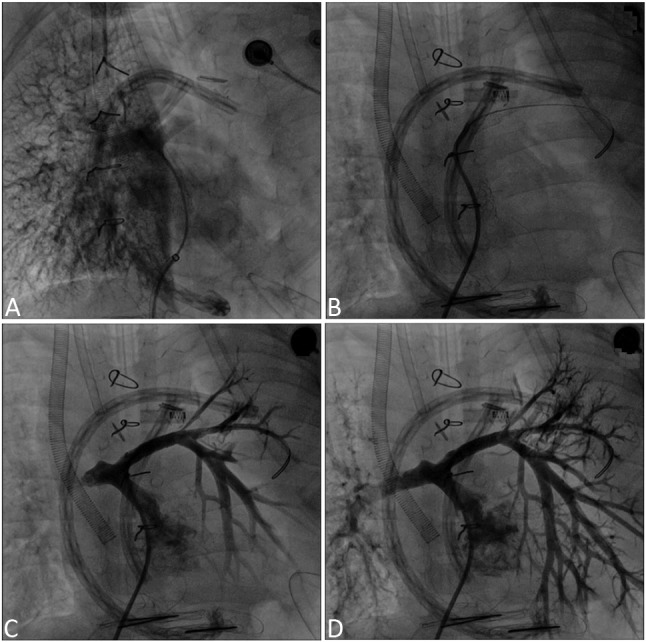

Diagnostic catheterization was performed in 24 cases (48%) and interventional procedures were carried out in 26 cases. Diagnostic catheterization was performed in 7 cases under ECMO support, and invasive procedures were used in 9 cases under ECMO support. Pulmonary artery dilatation was performed in 5 cases, pulmonary artery stenting in 5 cases, and major aortopulmonary collateral artery (MAPCA) embolization in 3 cases. The interventional data are demonstrated in Table 2, and Figure 1 shows procedural images of a case.

Figure 1.

Angiogram of a five-year-old boy diagnosed with double outlet right ventricle, ventricular septal defect and severe pulmonary stenosis. After cardiac surgery, ECMO support initiated. During ECMO support cardiac catheterization performed. (A) No antegrade flow in the left pulmonary artery. (B & C) Balloon and stent angioplasty of left pulmonary artery. (D) Increased left pulmonary artery flow after stent implantation.